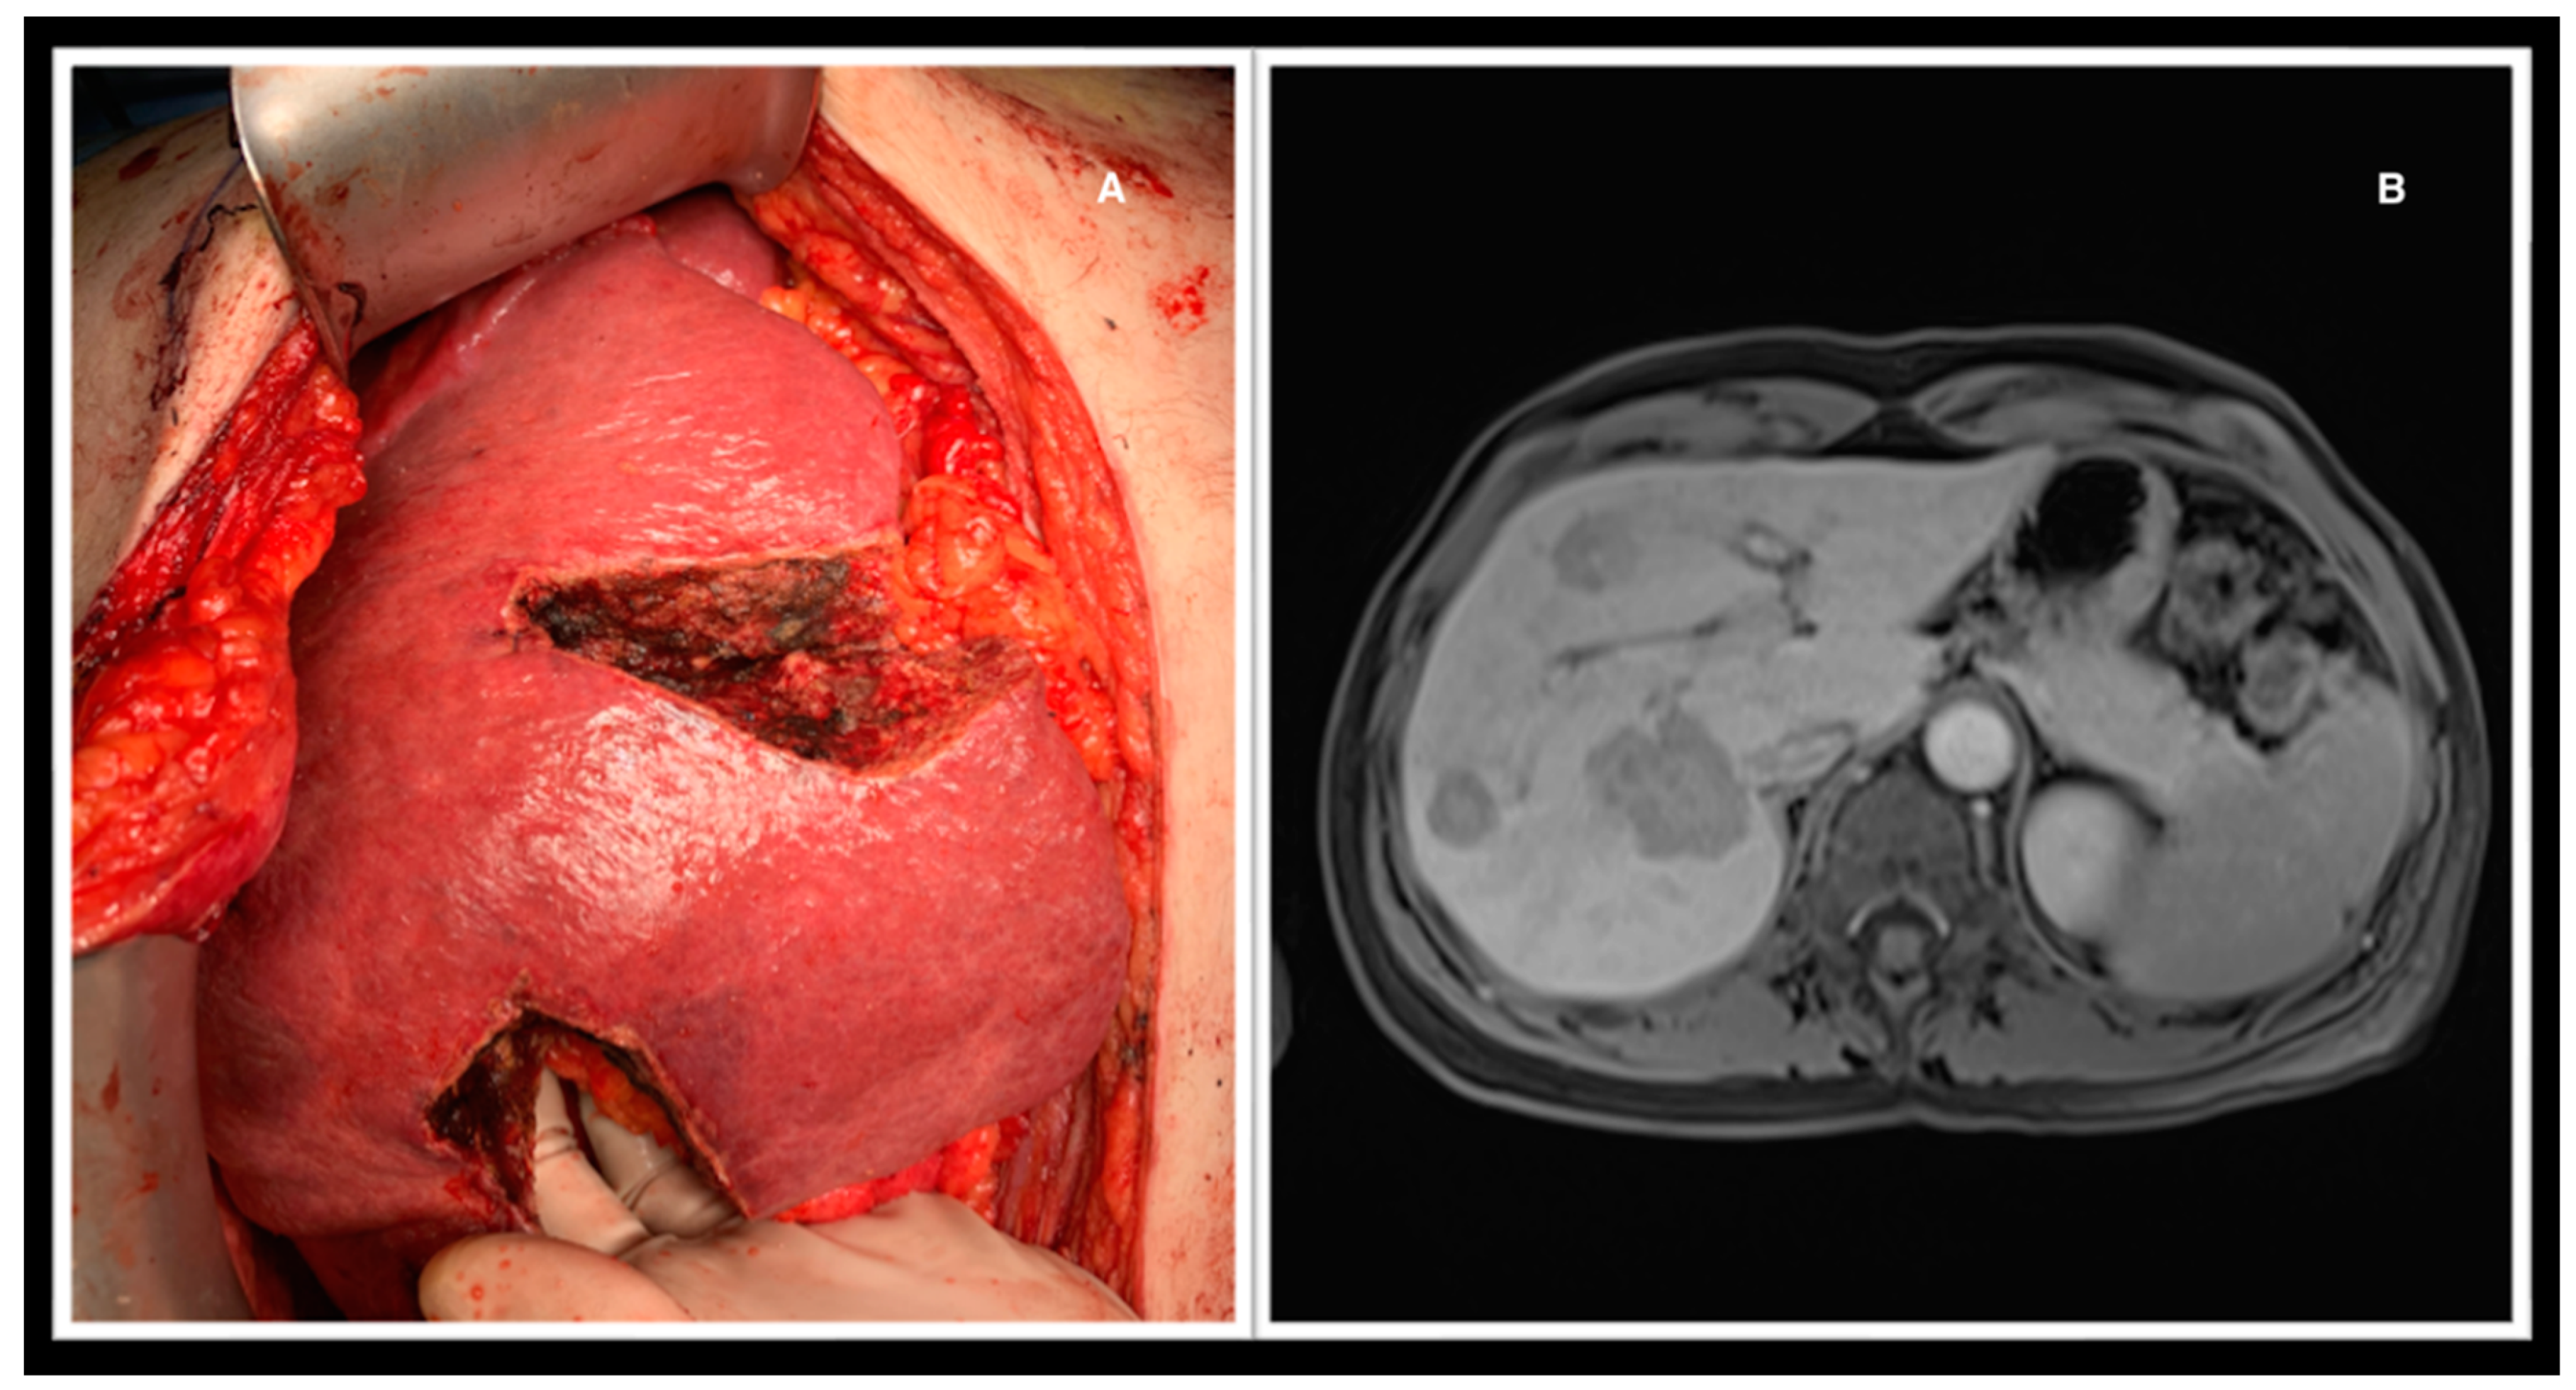

Figure 3. A: Atypical resection of liver metastases. B: The MRI depicts the lesions.

Hepatic resections were all performed in an open setting. The type of surgery to be performed was decided based on imaging examinations (CT, MRI, or both), anatomical complexity, and whether CRS+HIPEC was performed concomitantly. Operations performed included major hepatectomy (three or more liver segments; n=6), minor hepatectomy (less than three segments; n=6), atypical resection (n=26), and double-vein embolization (n=2) [11]. (Figure 1) (Figure 2) (Figure 3)